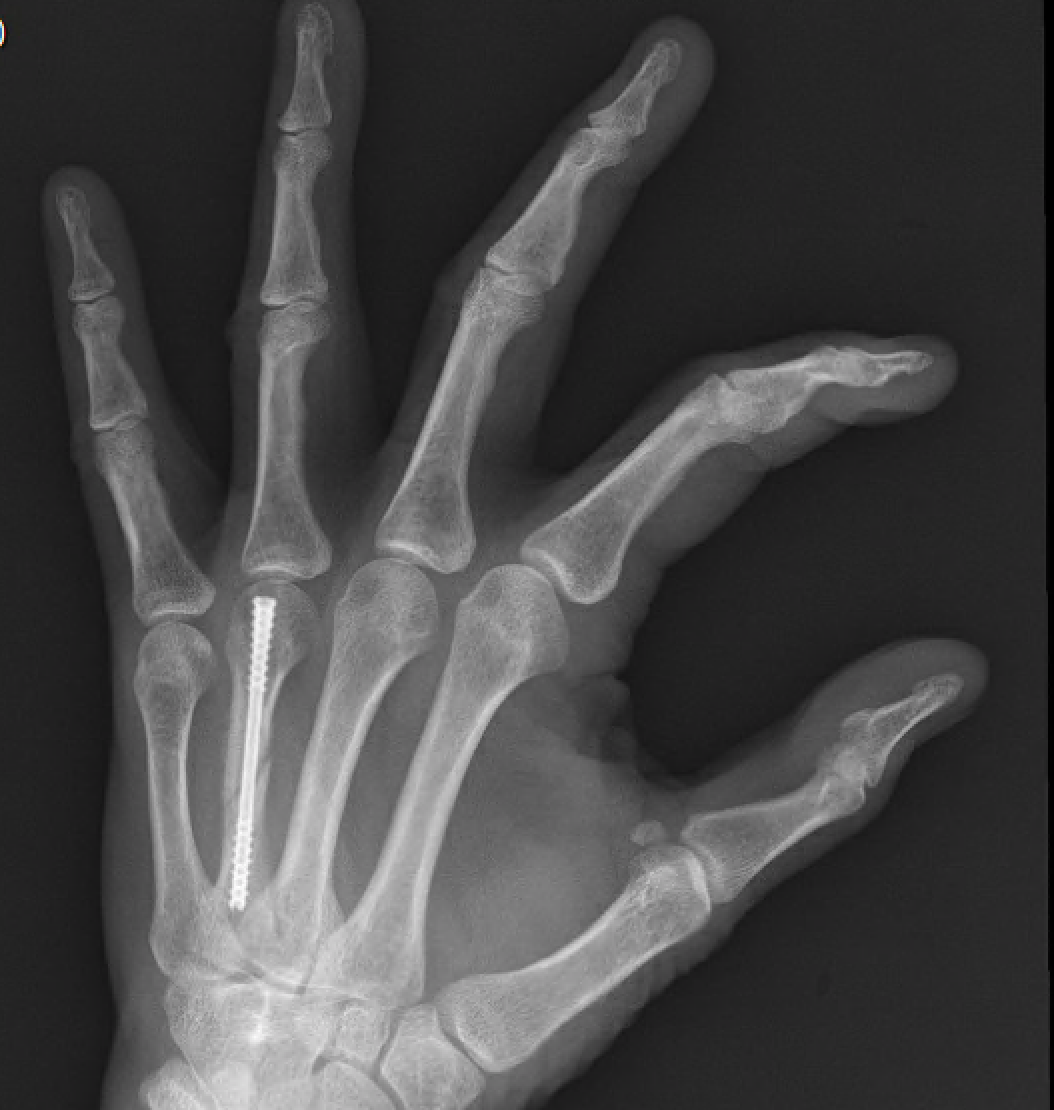

from fieldorthopaedics.com

NX Nail for fixation of spiral fracture of fourth metacarpal.